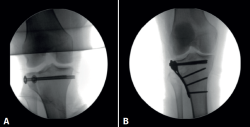

Injured knees always undergo anteroposterior and lateral plain radiographs. A CT scan is also essential for diagnosis, fracture pattern characterization (Figure 1), and surgery planning.

Figure 1. Right knee. Schatzker II close tibial plateau fracture. A: coronal computed tomography (CT) scan; B and C: 3-D tibial plateau fracture reconstruction.